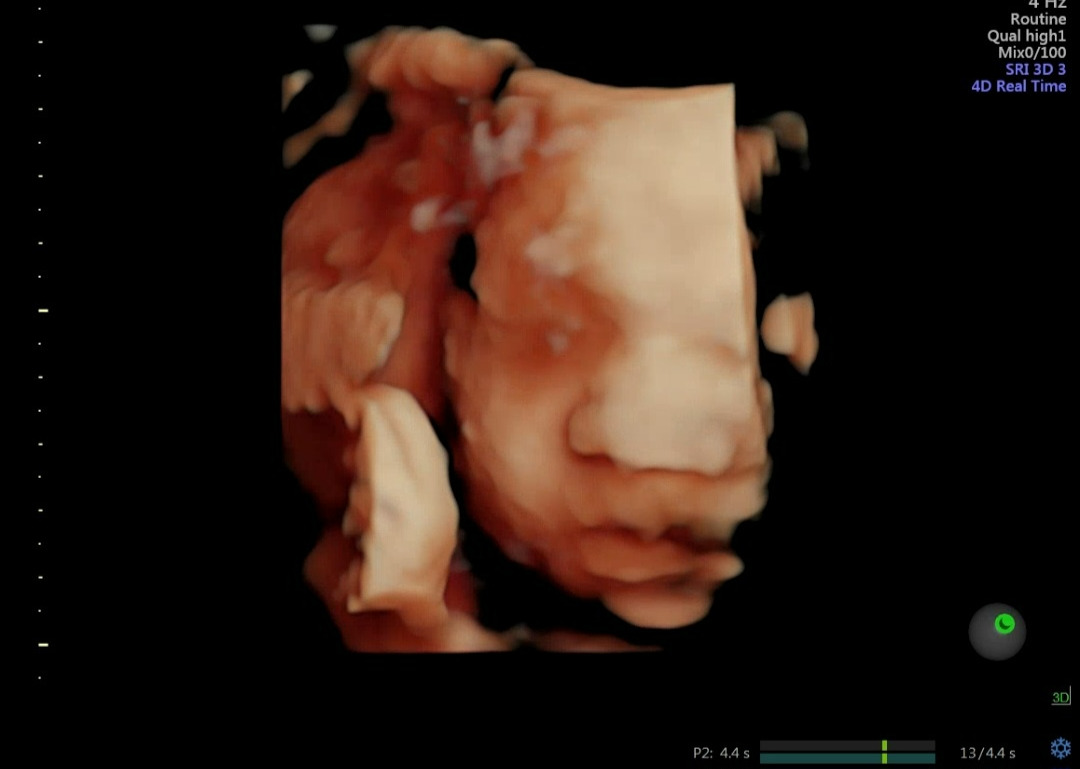

우리 아기는 어떻게 생겼을까?ㅎㅎ

그리고 37주초에 이슬이 비치기 시작했어. 갑자기 아주 작은 양의 피가 나왔거든. 엄마랑 아빠는 쫄아서 바로 병원에 달려 갔어! 집 앞이 바로 병원이라 편하다! 그런데 의사 선생님께서 초보 엄마 아빠에게 앞으로는 배가 아프면 오라고 하셨어. 지속적으로 이슬이 비칠 거라구. 그러면서, 왠지 반짝이는 일찍 나올 것 같진 않다고 안심시켜주셨어. 반짝이가 아직 2.4kg이라서 엄마 뱃속에서 조금이라도 더 무럭무럭 자라서 3kg에 태어났으면 좋겠거든. 38주부터는 이른둥이가 아니니까 일단 이번주만 건강하게 잘 넘겼으면 좋겠다 반짝아 ㅎㅎ